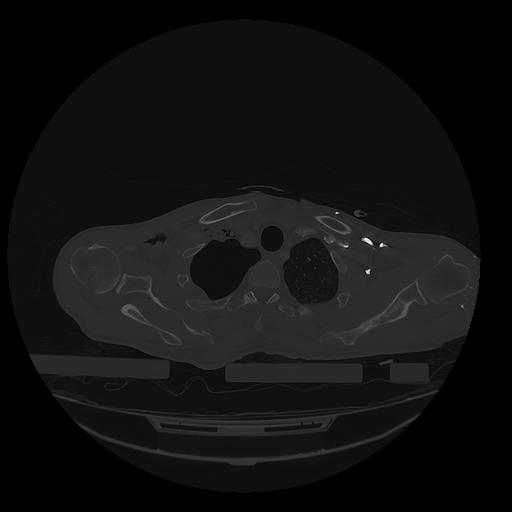

31 PULMON,CE,Vol,1.0,PULMON,,